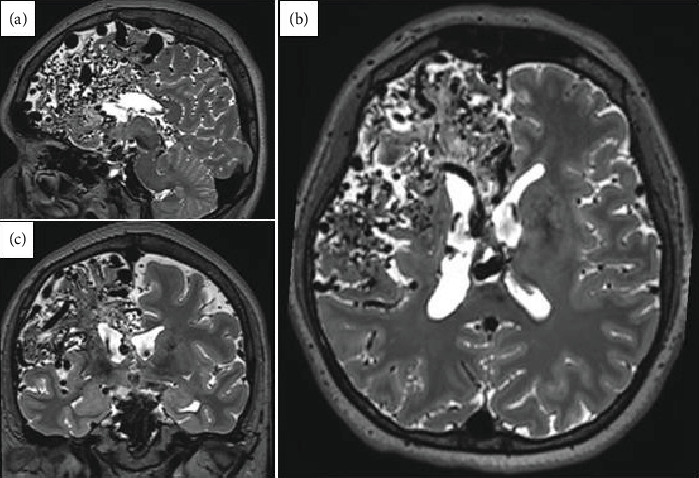

颅内动静脉畸形(AVMs)是一种血管异常,可表现为颅内出血、癫痫发作或神经功能缺损。在本病例中,我们报告了一名6岁时因脑出血而被诊断为巨大右额顶叶AVM (Spetzler-Martin Grade V)的女性。由于病变的大小和明显的位置,手术、血管内和放射外科治疗都不可行。随着时间的推移,患者出现局灶性癫痫发作,包括先天性畸形和左臂痉挛性单眼。最初的抗癫痫药物如卡马西平和苯妥英在最佳剂量下不能提供足够的控制,苯妥英加剧了癫痫发作的频率。通过左乙拉西坦和卡马西平的联合治疗,最终实现了部分癫痫发作的控制。神经影像学显示大的动静脉畸形,脑电图显示局灶性癫痫样活动。这个病例说明了治疗巨大心房动静脉畸形继发癫痫的复杂性,强调了个体化心房动静脉畸形策略和协作、多学科管理的必要性。

Intracranial arteriovenous malformations (AVMs) are vascular anomalies that can present with intracranial hemorrhage, seizures, or neurological deficits. In this case, we present a woman with a giant right frontoparietal AVM (Spetzler-Martin Grade V) initially diagnosed after an intracerebral hemorrhage at Age 6. Surgical, endovascular, and radiosurgical treatments were not viable due to the lesion's size and eloquent location. Over time, the patient developed focal seizures, including catamenial patterns and left-arm spastic monoparesis. Initial antiseizure medications (ASMs) such as carbamazepine and phenytoin failed to provide adequate control at optimal dosage, with phenytoin exacerbating seizure frequency. Partial seizure control was eventually achieved with a combination of levetiracetam and carbamazepine. Neuroimaging showcases a large AVM, while EEG revealed focal epileptiform activity. This case illustrates the complexity of treating epilepsy secondary to giant AVMs, emphasizing the need for individualized ASM strategies and collaborative, multidisciplinary management.